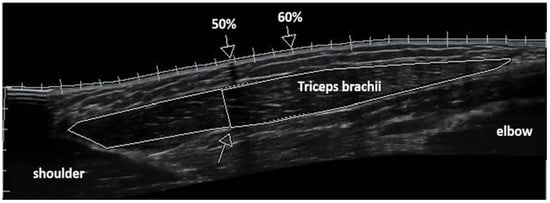

Figure 1. Panoramic sonographic image of triceps brachii muscle. Perimeters of the long head of triceps are shown represented longitudinal muscle area (total, distal, proximal). The arrow on the deep aponeurosis of the long head shows the anatomical point where the middle head joins the long head, which was selected to separate the muscle area as distal (closer to elbow) and proximal (closer to shoulder). Arrows on the superficial aponeurosis show where muscle thickness, pennation angle, and fascicle length were measured at 50% and 60% of the upper-arm length.

All ultrasound measurements before and after training were performed during the morning hours and after subjects remained supine for 20 min to allow fluid shifts to occur [12]. Pre-training ultrasound images were obtained before the familiarization sessions and maximum strength tests, while the post-training ultrasound images were obtained 5 days after the last training session and 3 days after performing the maximum strength tests, in order to avoid osmotic fluid shifts that may confound architectural or morphological measurements. Panoramic B-mode ultrasound images were obtained with a 38-mm linear probe from the long head of the triceps brachii using the “i-scape” software of the ultrasound device (10.0-MHz, Product model Z5, Shenzhen, Mindray Bio-Medical Electronics Co., Ltd., Shenzhen, China). Initially, participants were placed at a standing position with their arms fully extended to the side of the body. The posterior surfaces of the acromion and the lateral epicondyles of the humerus were marked and used as the total length of the upper arm [13]. The upper arm (starting from acromion) was marked at 50% and 60% of the upper-arm length with a permanent pen. Self-adhesive paper was placed on the skin at these two points as a marker (image shadowing). Then, participants laid supine with their arms rested on a laboratory bed at 90° to their torso, fully extended on elbow joint and supinated. Participants were asked to isometrically contract their triceps, so that the researcher could locate the insertion of the triceps long head using the ultrasound image. Then, the transducer was placed laterally to the arm and oriented in parallel to the muscle fascicles. The transducer’s alignment was considered appropriate when several fascicles could be easily outlined without interruption across the image. The fascicle path was drawn on the skin with a pen according to the fascicle path seen from the real-time ultrasound image. To obtain the panoramic image, a continuous single view was taken by moving the probe along the marked line [14]. Images were analyzed (as previously aforementioned) for muscle thickness, fascicle angle, and fascicle length at 50% and 60% of the upper-arm length [14]. The two-dimensional longitudinal muscle area was calculated in three regions: total, distal, and proximal with image analysis software (Motic Images Plus 2.0, Motic, Hong Kong, China). Longitudinal muscle area was measured using the “polygon” tool of the image analyzing program to analyze the total, proximal, and distal area of the long head of triceps brachii. In each sonographic image, an anatomical point of the deep aponeurosis was identified where the mid triceps head joins the long head. This anatomical point was selected in order to separate the distal (closer to the elbow) and proximal area (closer to shoulder) of the muscle (Figure 1).